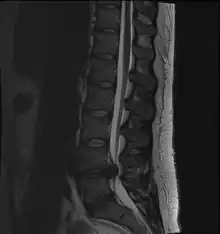

- Magnetic resonance imaging is the gold standard study for confirming a suspected LDH. With a diagnostic accuracy of 97%, it is the most sensitive study to visualize a herniated disc due to its significant ability in soft tissue visualization. MRI also has higher inter-observer reliability than other imaging modalities. It suggests disc herniation when it shows an increased T2-weighted signal at the posterior 10% of the disc. Degenerative disc diseases have shown a correlation with Modic type 1 changes. When evaluating for postoperative lumbar radiculopathies, the recommendation is that the MRI is performed with contrast unless otherwise contraindicated. MRI is more effective than CT in distinguishing inflammatory, malignant, or inflammatory etiologies of LDH. It is indicated relatively early in the course of evaluation (<8 weeks) when the patient presents with relative indications like significant pain, neurological motor deficits, and cauda equina syndrome. Diffusion tensor imaging is a type of MRI sequence used for detecting microstructural changes in the nerve root. It may be beneficial in understanding the changes that occur after herniated lumbar disc compresses a nerve root, and might help in differentiating the patients that need surgical intervention. In patients with a high suspicion of radiculopathy due to lumbar disc herniation, yet the MRI is equivocal or negative, nerve conduction studies are indicated.[43] T2-weighted images allow for clear visualization of protruded disc material in the spinal canal.

A rather severe herniation of the L4–L5 disc

Example of a herniated disc at L5–S1 in the lumbar spine